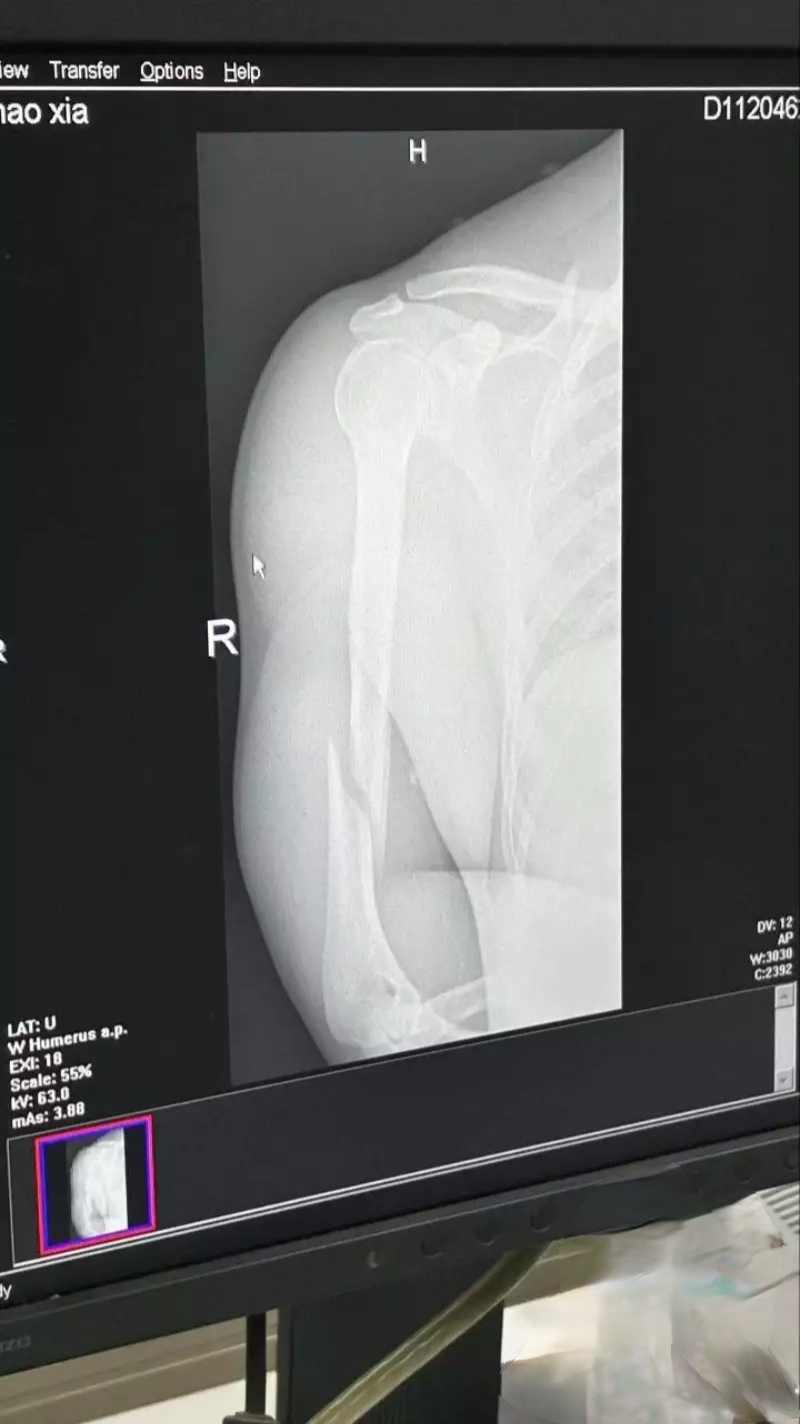

腱子肉猛男刚秀完杠铃硬拉,转头就跟人掰腕子争霸王结果悲剧了……

腱子肉猛男刚秀完杠铃硬拉,转头就跟人掰腕子争霸王……